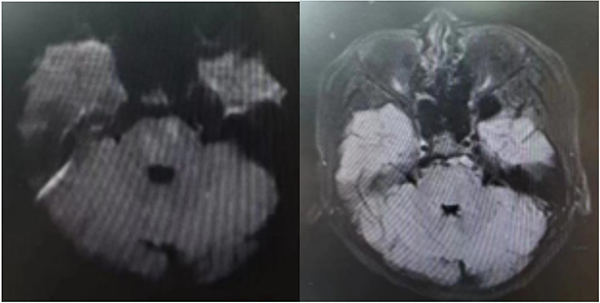

患儿到院后立即完善头颅核磁检查提示:脑桥、双侧小脑半球多发异常信号,多考虑脑梗死(急性期);基底动脉及双侧椎动脉颅内段局部未显影,多考虑闭塞。卒中中心启动绿色通道评估。